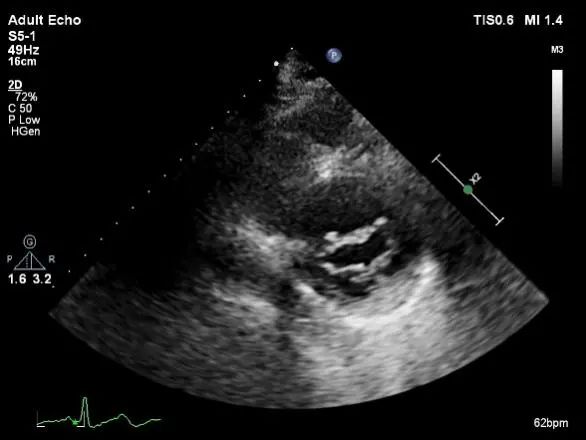

TEE短轴脱垂区域显示(P2、P3区大范围脱垂)

TEE短轴脱垂区域显示(color,血流来源于P2、P3区)

肺静脉收缩期反向血流

平均跨瓣压差:5mmHg